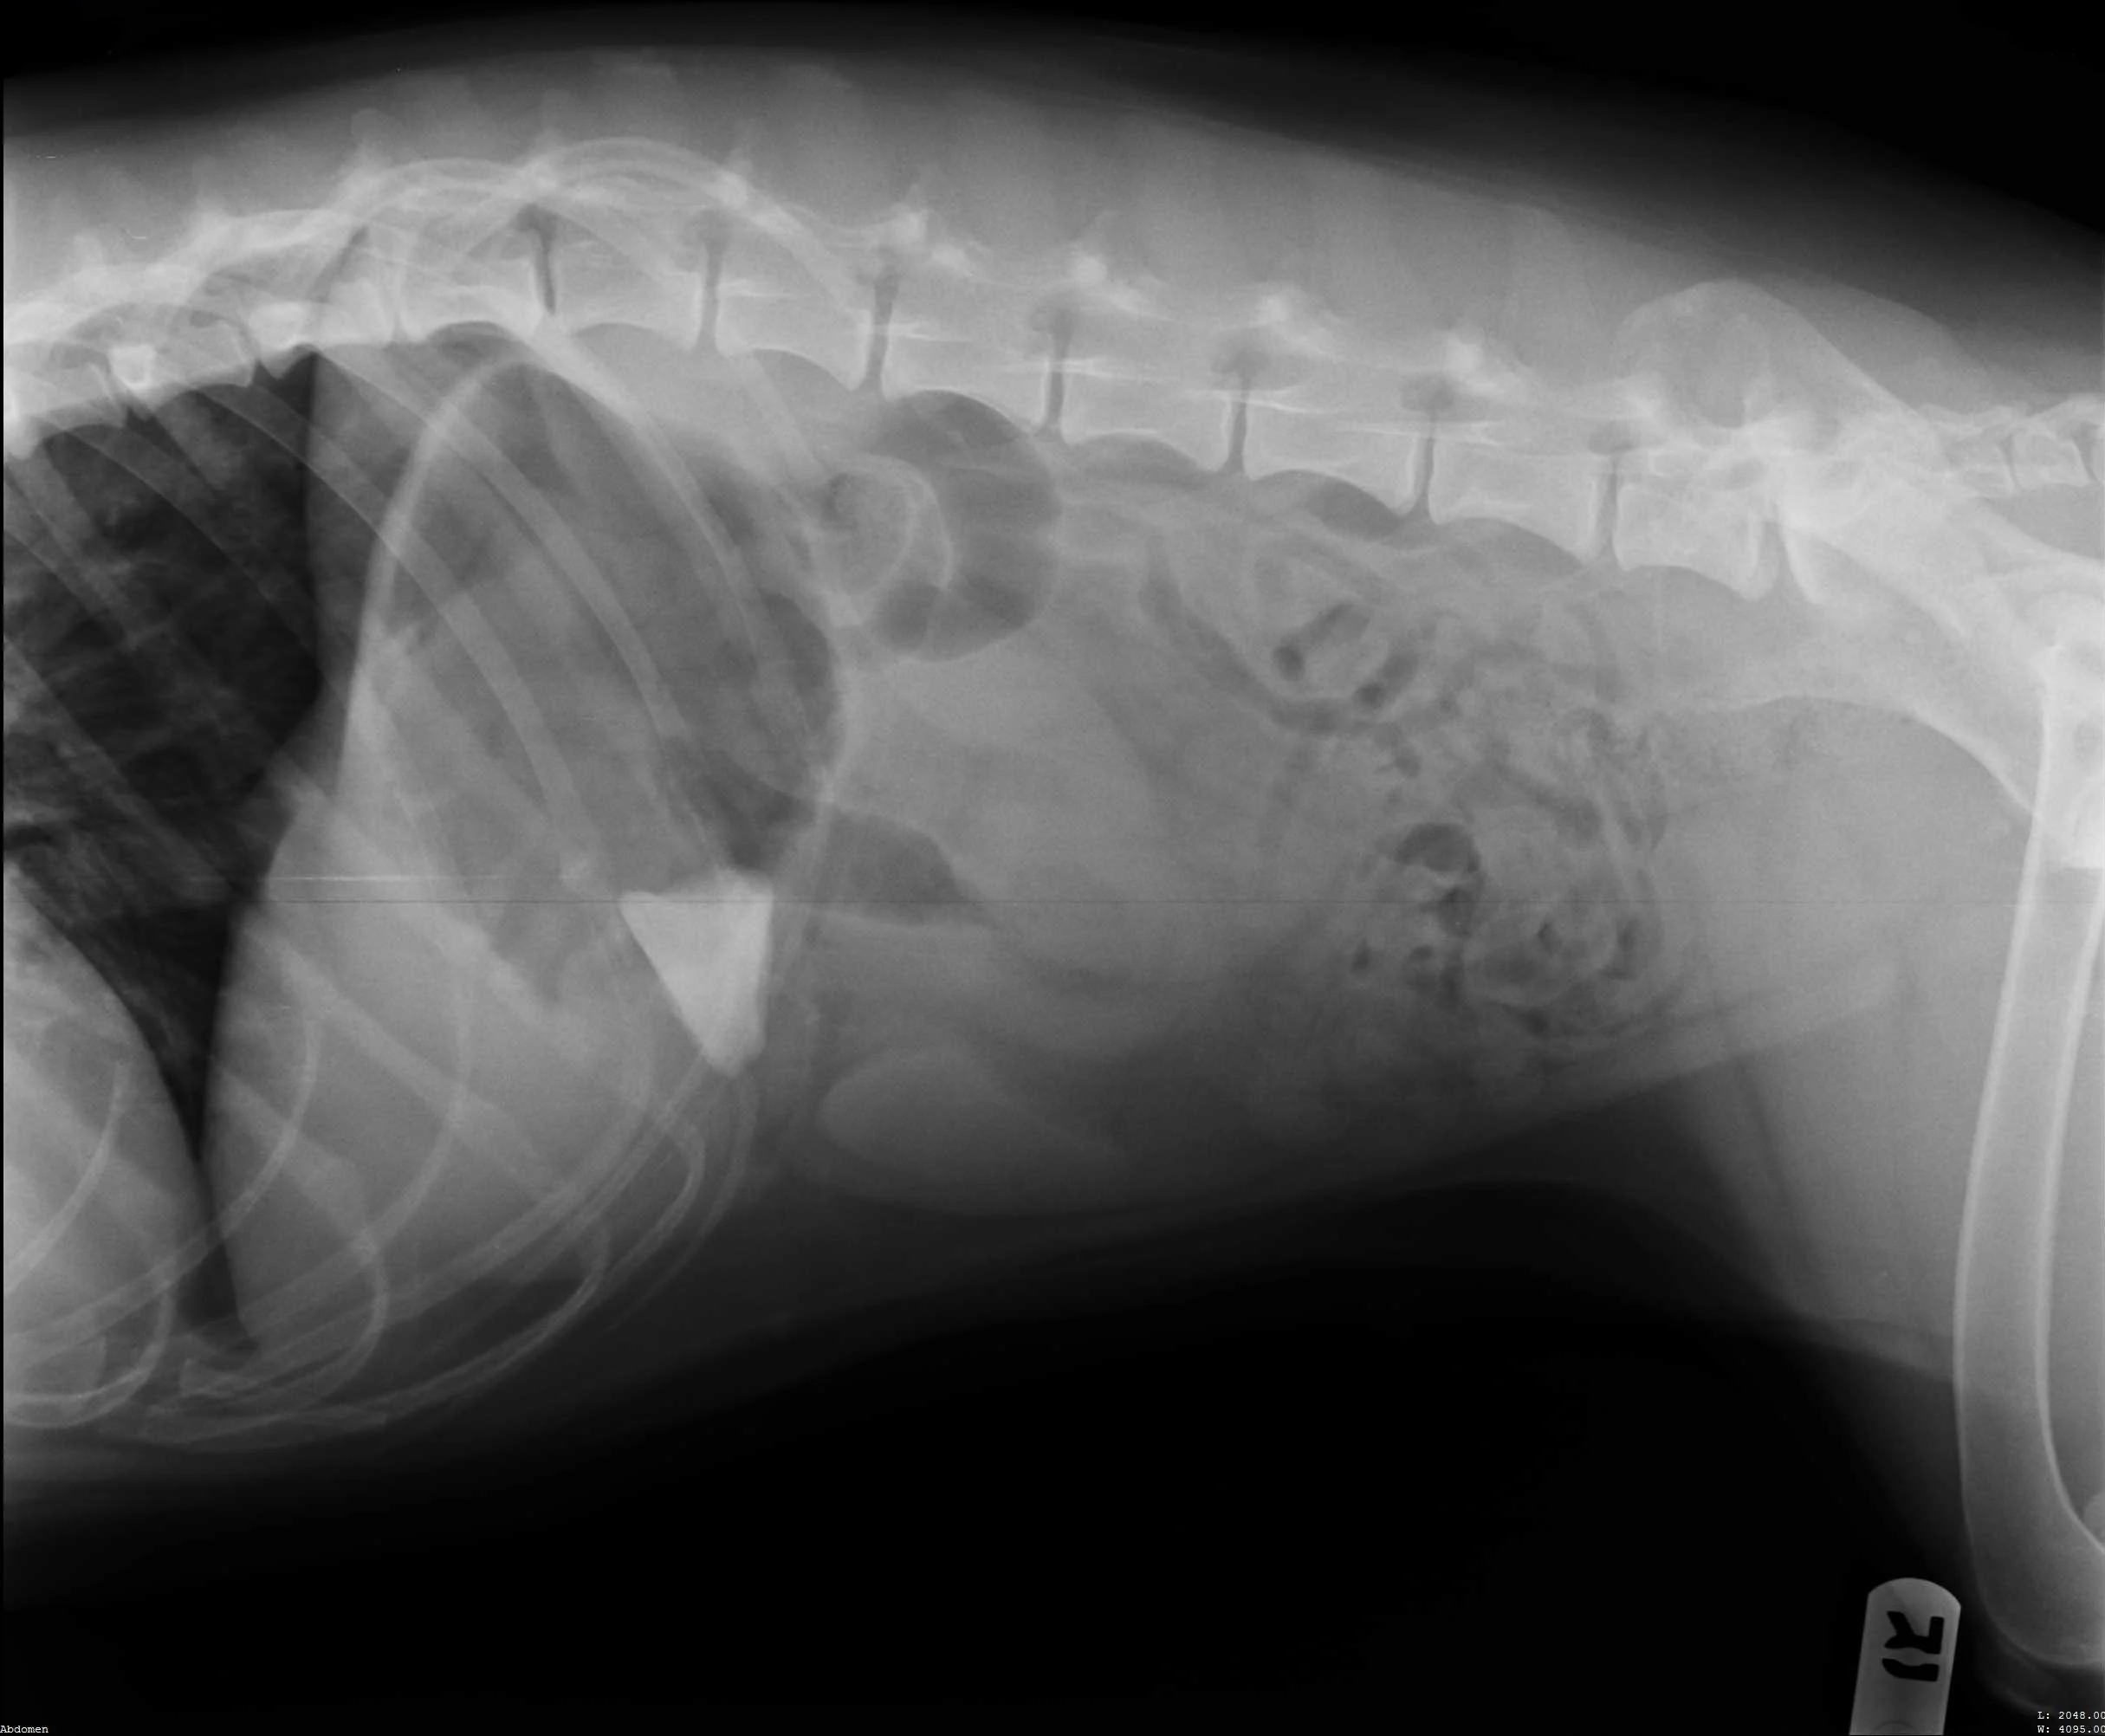

Abdominal radiographs revealed a rock in the patient’s stomach, leading to a diagnosis of a gastric foreign body with outflow obstruction and a secondary finding of megaesophagus.

Right lateral abdomen